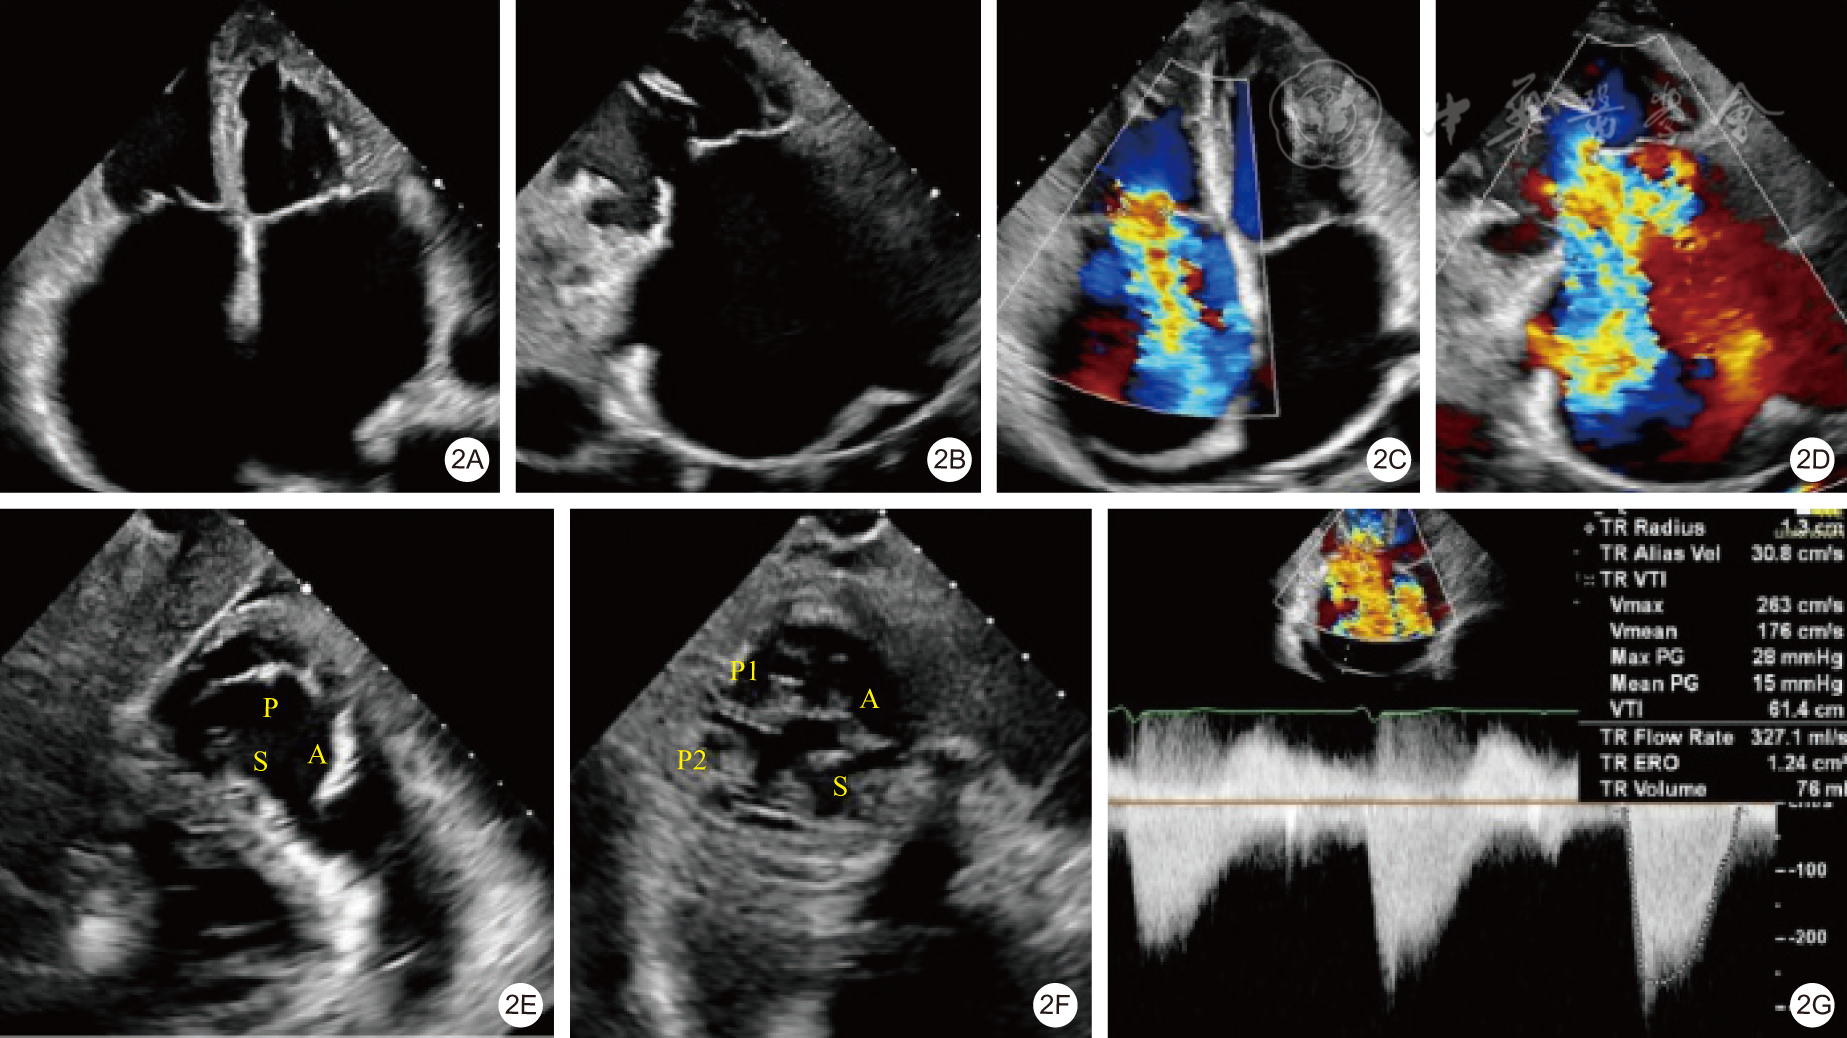

图5 着陆区与锚定点(5A. 着陆区;5B. 锚定点)